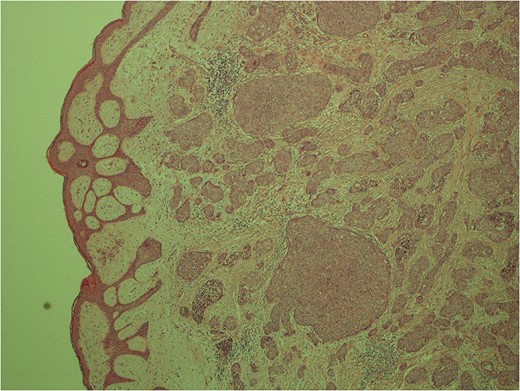

Low power image demonstrating the skin surface and dermal nests of tumour completely filling the tissue.